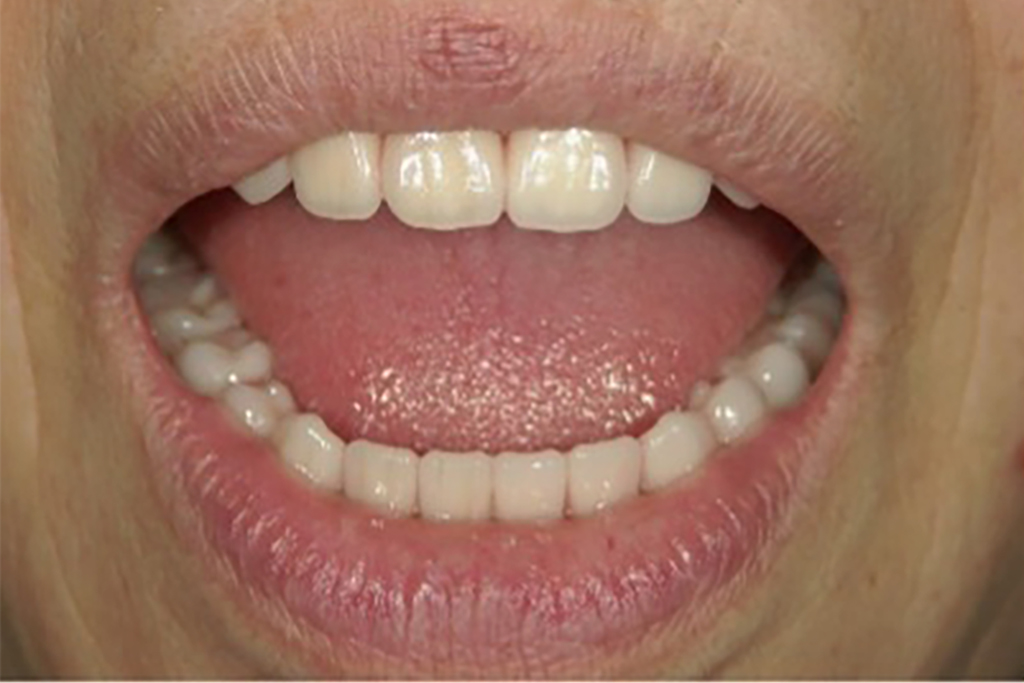

入れ歯の試適

• 兵庫県南あわじ市・医療法人 太田歯科・矯正歯科

完成前に入れ歯の適合試験を行います。

入れ歯が安定しているか、装着した際のお顔の表情・口元に歪が生じないかなど、生体と調和しているかどうかを確認します。